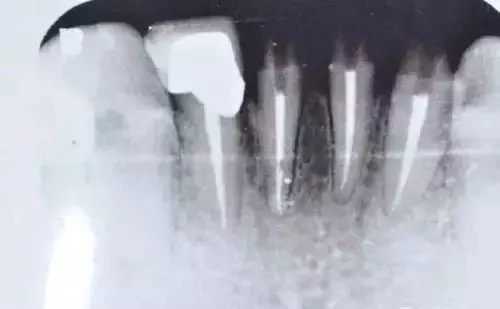

劉小姐的烤瓷牙在使用了六年之后,雖然仍能夠正常飲食,但卻一直斷斷續(xù)續(xù)出現(xiàn)牙痛的癥狀,靠吃著消炎藥來緩解疼痛。直到前不久,劉小姐發(fā)現(xiàn)左邊上排的烤瓷牙出現(xiàn)松動(dòng),于是才到醫(yī)院進(jìn)行檢查。經(jīng)過檢查發(fā)現(xiàn),她的牙冠內(nèi)存在的基牙都已經(jīng)全部發(fā)炎,并開始腐爛,只能拔除剩余的腐爛基牙,做全口固定的種植牙。